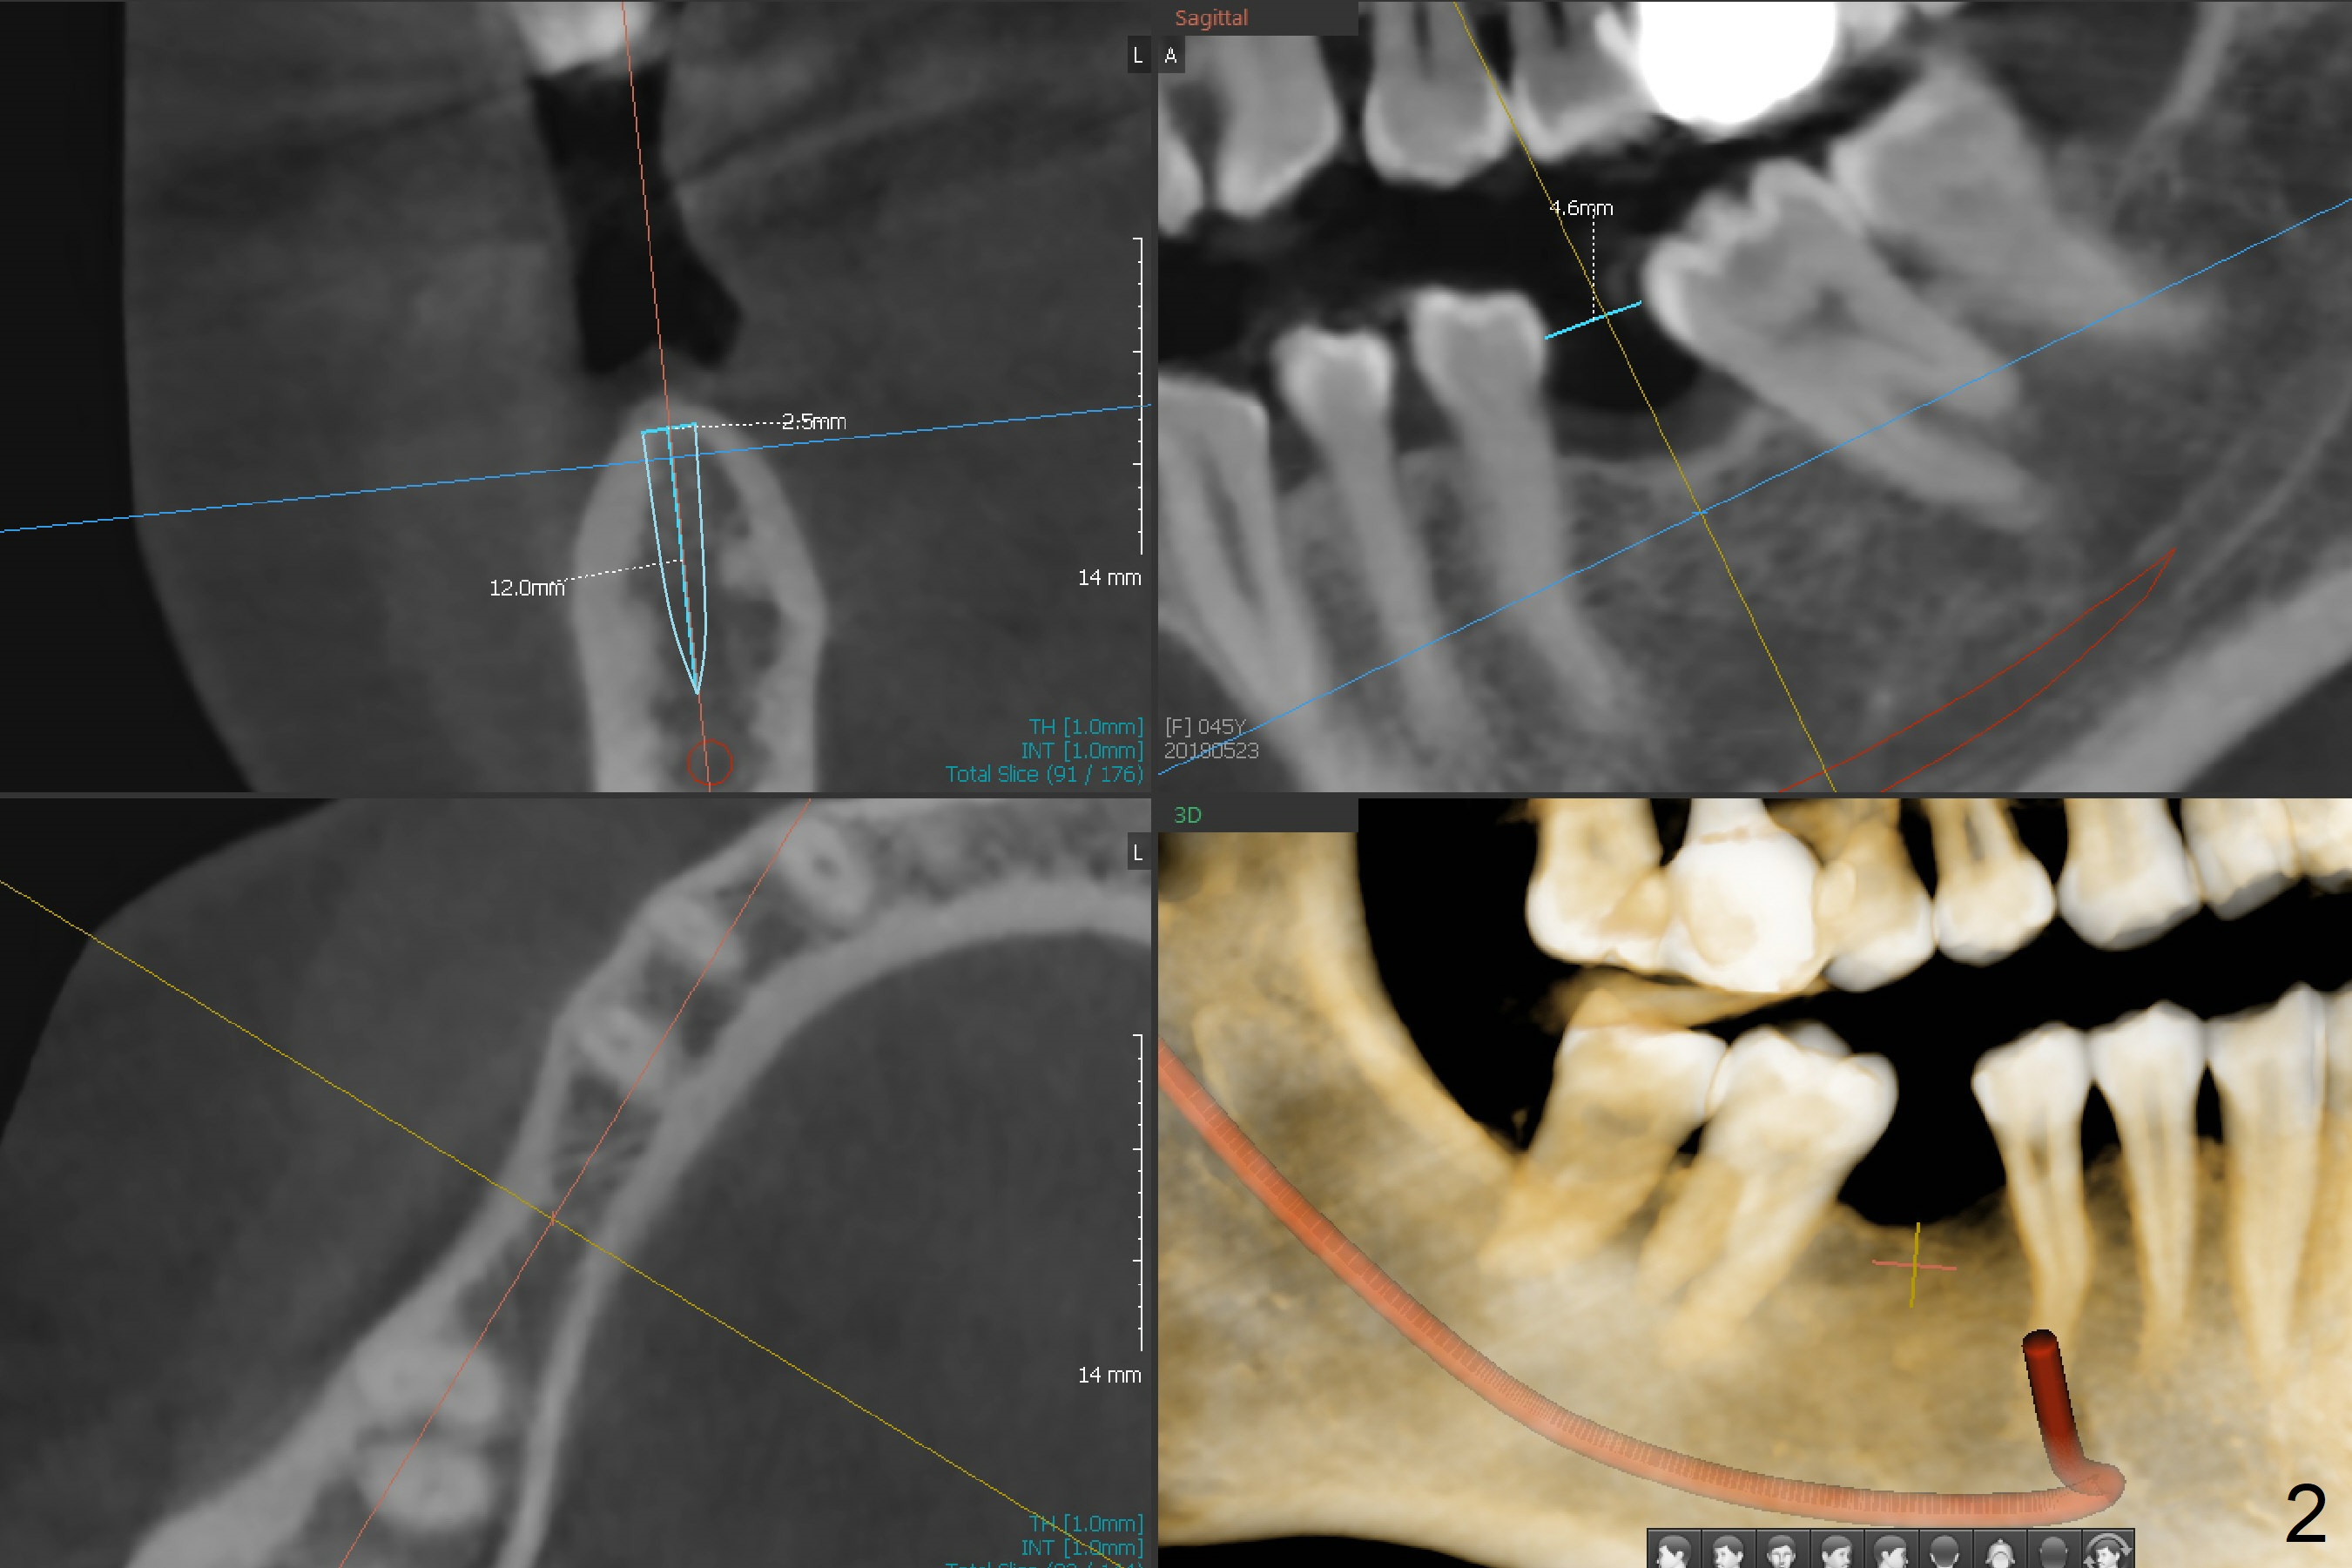

2.5 mm Implant at 1st Molar A 45-year-old woman requests an implant at #30 immediately post #3 implant cementation (Fig.1). She is reluctant to have #32 extraction for ortho. After trimming #29 distal and #31 mesial surfaces, a 2.5x12 mm implant will be placed using a tissue punch in the kit (Fig.2,3). Prepare the Regular and Basic Implant Cassettes. Return to

Lower

Molar Immediate Implant, Armaments Xin Wei, DDS, PhD, MS 1st edition 05/23/2018, last revision 06/01/2018 |